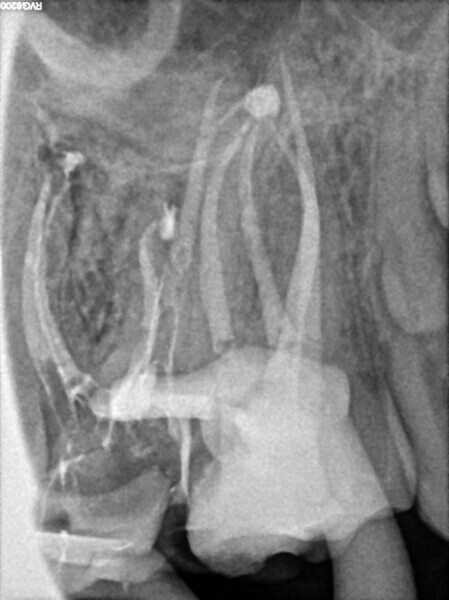

Case 2 (Figs. 27–36)

A 25-year-old female patient presented to the office owing to constant pain related to the mandibular left first molar. Pulp necrosis was diagnosed. After the emergency appointment, the patient was referred for complete treatment. The tooth was treated in the same manner as described in the previous paragraphs. After creation of the access cavity, the orifices were located. In the root chamber, the orifices of the MB, mesiolingual, DB, distomesial and distolingual canals were present. After pre-flaring and preparation of the middle third, the LPE enhanced irrigation protocol with the SkyPulse laser was performed. After the irrigation protocol in the mesial root, the irrigants started to flow between lingual and buccal canals. Such an observation suggested to the operator that some space in the isthmus had been created. It is worth mentioning that at this stage apical enlargement was not performed. Final preparation of all five canals was performed with the reciprocating file, and the final irrigation protocol was performed as in the previous case. The radiograph clearly revealed that the isthmus space was filled with the sealer. The radiograph and CBCT image revealed that there were four portals of exit in the mesial root.